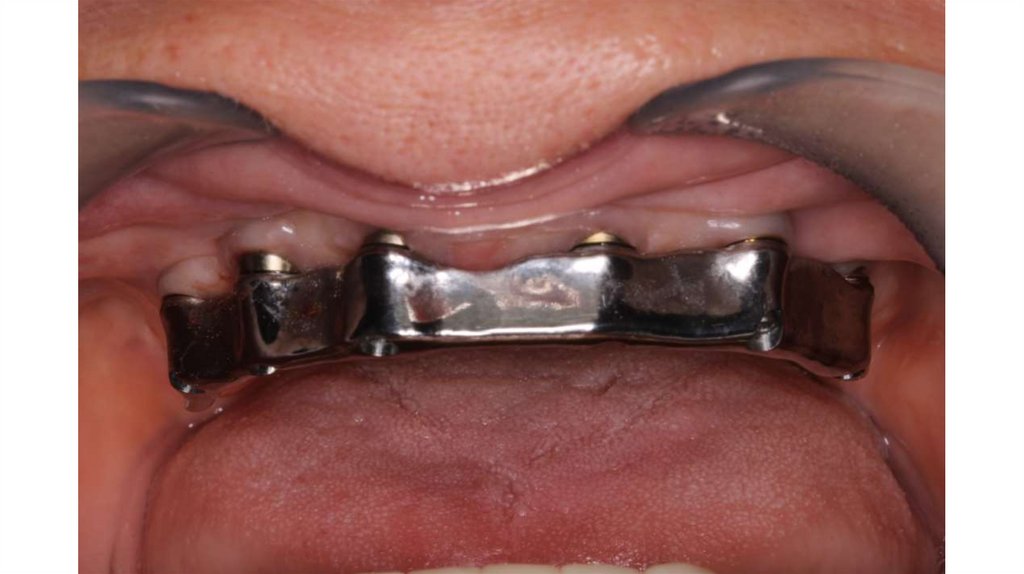

• Мне важно ваще мнение такие щели между мультиюнитом и

каркасом должны быть???

• Мне лично кажется – что должно быть все «заподлицо», но

возможно я ошибаюсь.